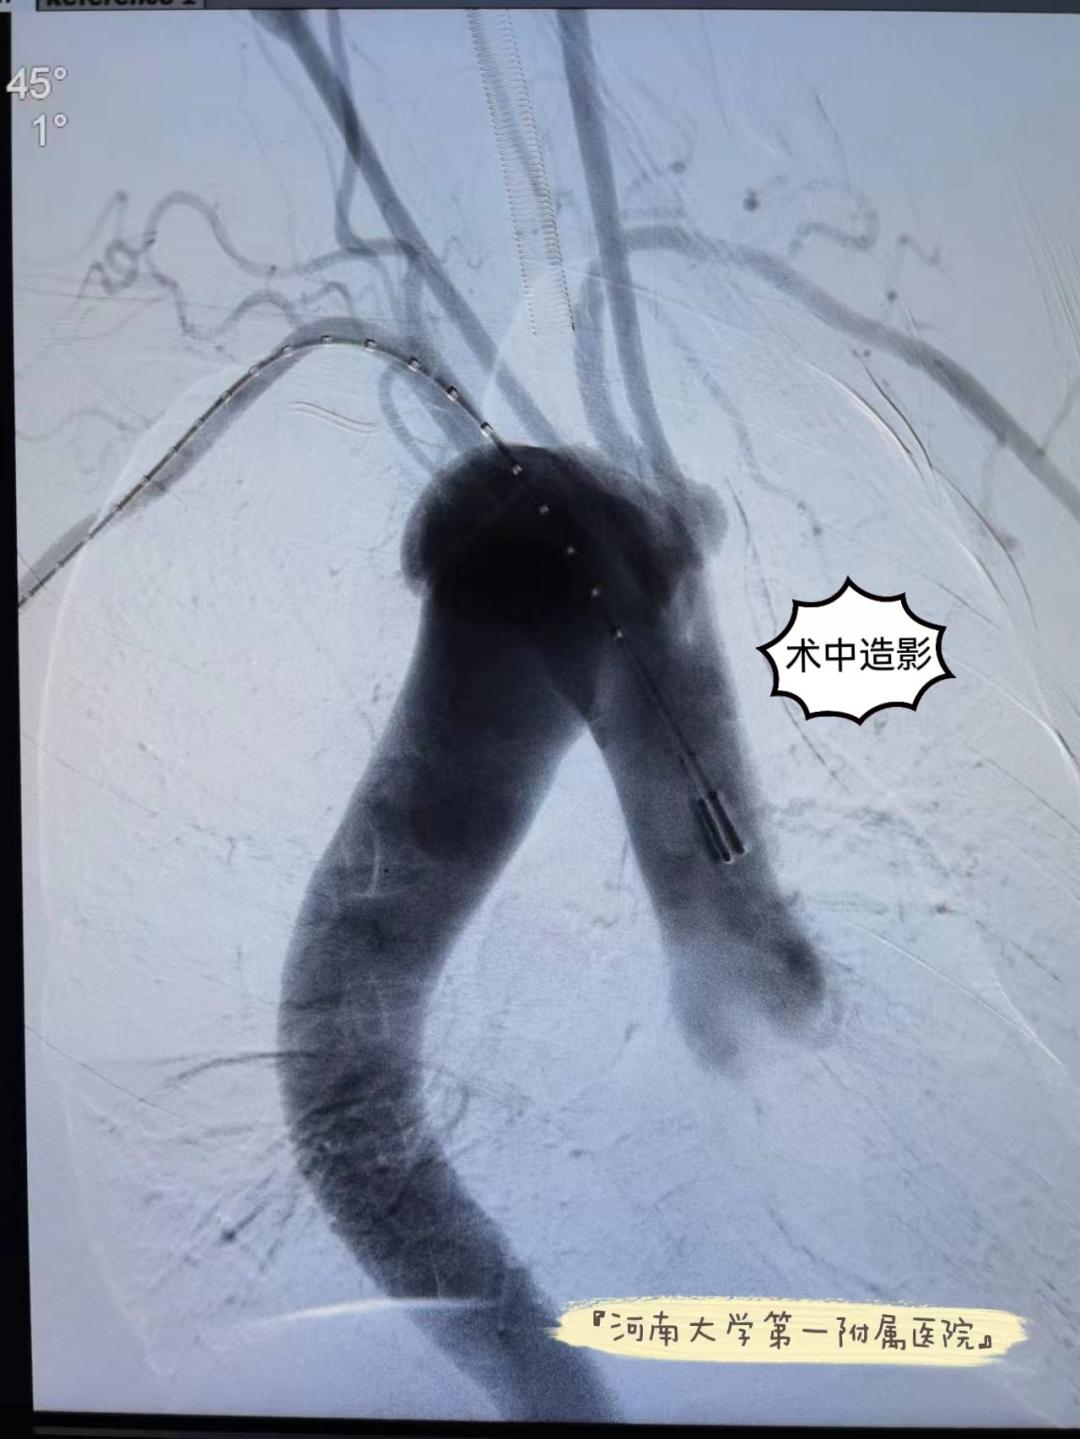

术中造影

经过术前的精心准备,在麻醉与围术期医学科、手术部的保驾护航下,心血管外科团队在张双林、郑先杰的指导下为患者实施手术。该手术较为复杂,难度很大,难点在于破口就位于左锁骨下动脉处,又有大动脉畸形,手术需要不同角度造影才能把主动脉弓上血管显现出来,既要定位准确,还要开窗超选右锁骨下动脉,同时要对左锁骨下动脉栓塞。孟庆江带领手术团队结合术前及术中精确测量结果于覆膜支架近心端10mm处行体外开窗、弹簧圈标记、内嵌分支,并利用束颈技术将支架改装成功后,经右侧股动脉输送至右颈总动脉后缘,完整释放大支架,后经左肱动脉导丝超选右锁骨下动脉,释放小支架重建右锁骨下动脉,最后用弹簧圈栓塞左锁骨下动脉,经过大家共同努力,手术顺利完成。